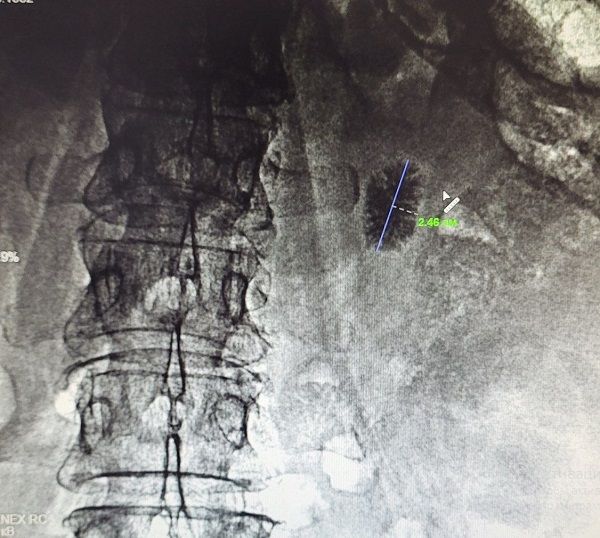

Уникальная операция в Бурятии: события и детали